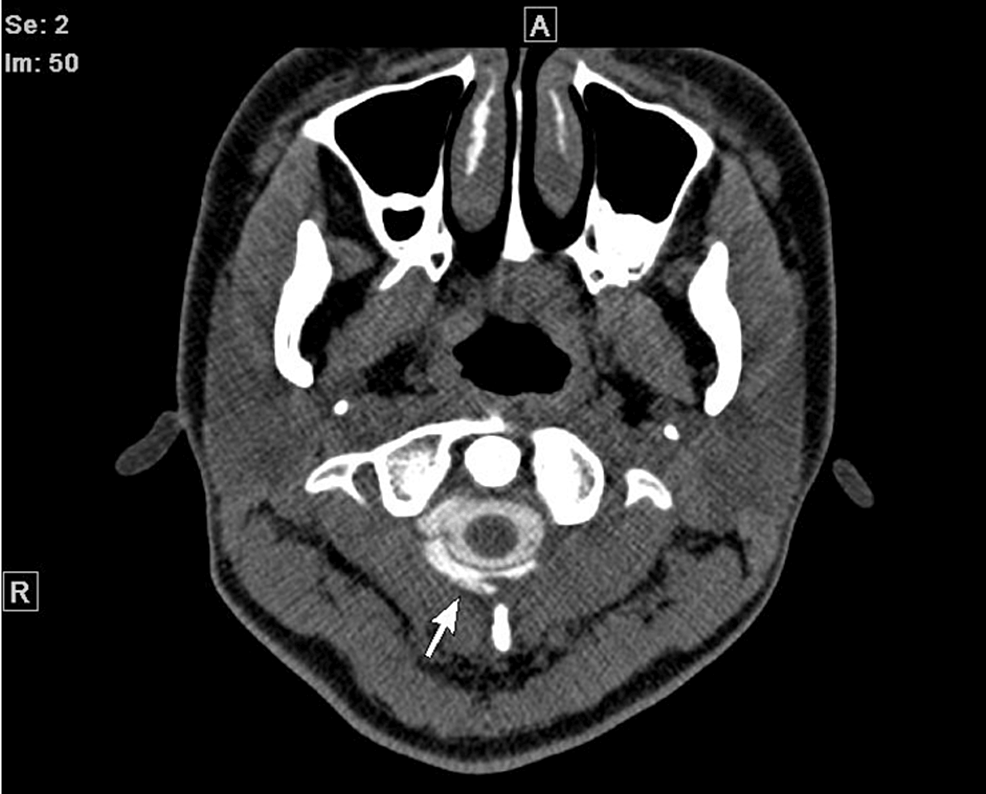

- コンピューター断層撮影 (CT)